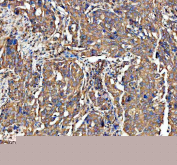

IHC staining of FFPE human ovarian serous adenocarcinoma tissue with ADAM10 antibody, HRP-secondary and DAB substrate. HIER: boil tissue sections in pH8 EDTA for 20 min and allow to cool before testing.